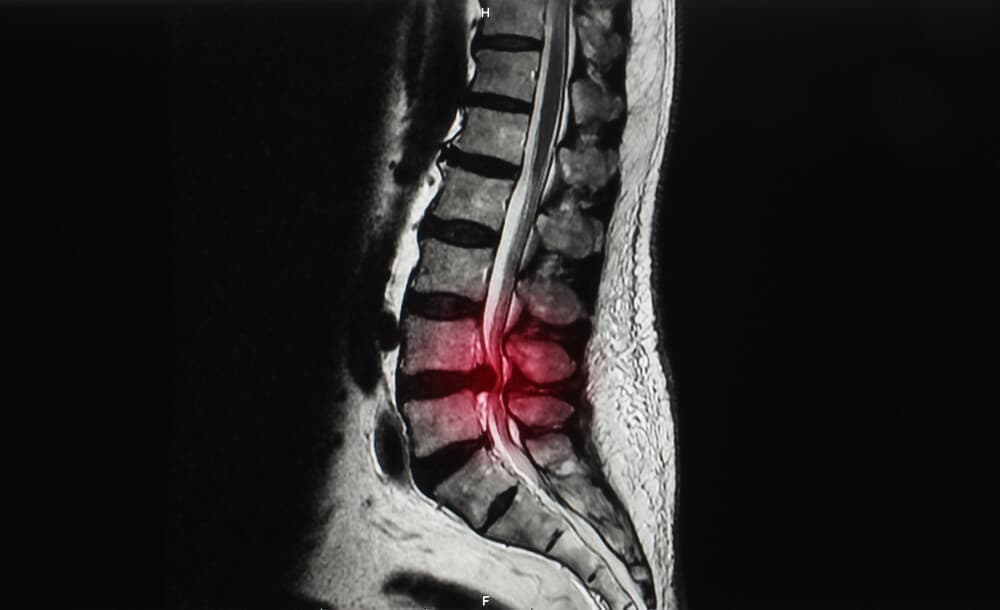

Before

After